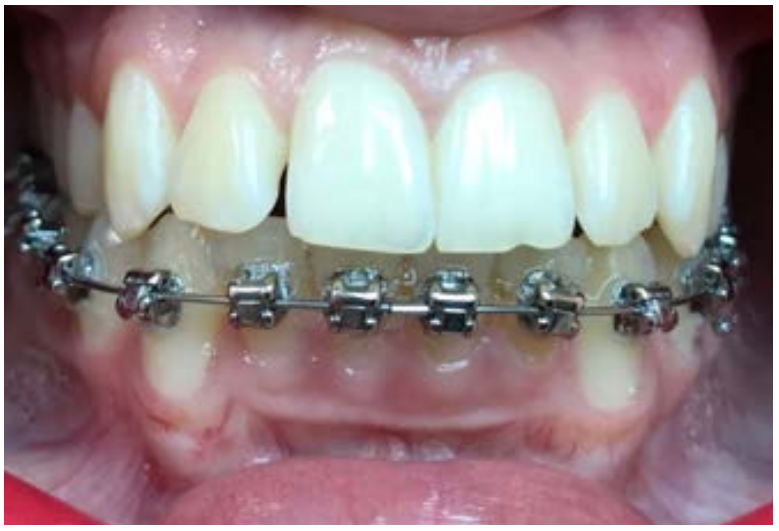

Обращает на себя внимание тот факт, что при перемещении нижних зубов лингвально из лабиальной позиции, т.е. при устранении протрузии, происходило уменьшение РД без ее пластики, на наш взгляд, за счет утолщения слизистой оболочки. В таких случаях хирургическая коррекция не проводилась. Этот процесс мы наблюдали у 3 растущих пациентов. При постоянном прикусе у пациентов с РД преобладает скученность резцов и тонкий биотип слизистой оболочки десны. Поэтому хирургическая подготовка перед ортодонтическим лечением заключалась в изменении биотипа десны путем пластики свободным соединительнотканным лоскутом. Далее лечение проводили на несъемной безлигатурной технике, с применением адекватных сил (рис. 5).

Рис. 5. Тот же пациент на этапе лечения несъемной техникой